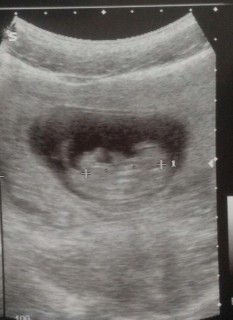

初の妊婦検診。2.7センチでした。11日ぶりにエコーで見たら、ちょうど診察の時に動く時間だったらしくハッキリしてきた手と足をいっぱい動かしてて可愛かった♡ 次の検診まで3週間…また不安な日が続くのか…でも我が子を信じよう

手足がピコピコ動いていて感動!

順調と言われて一安心。